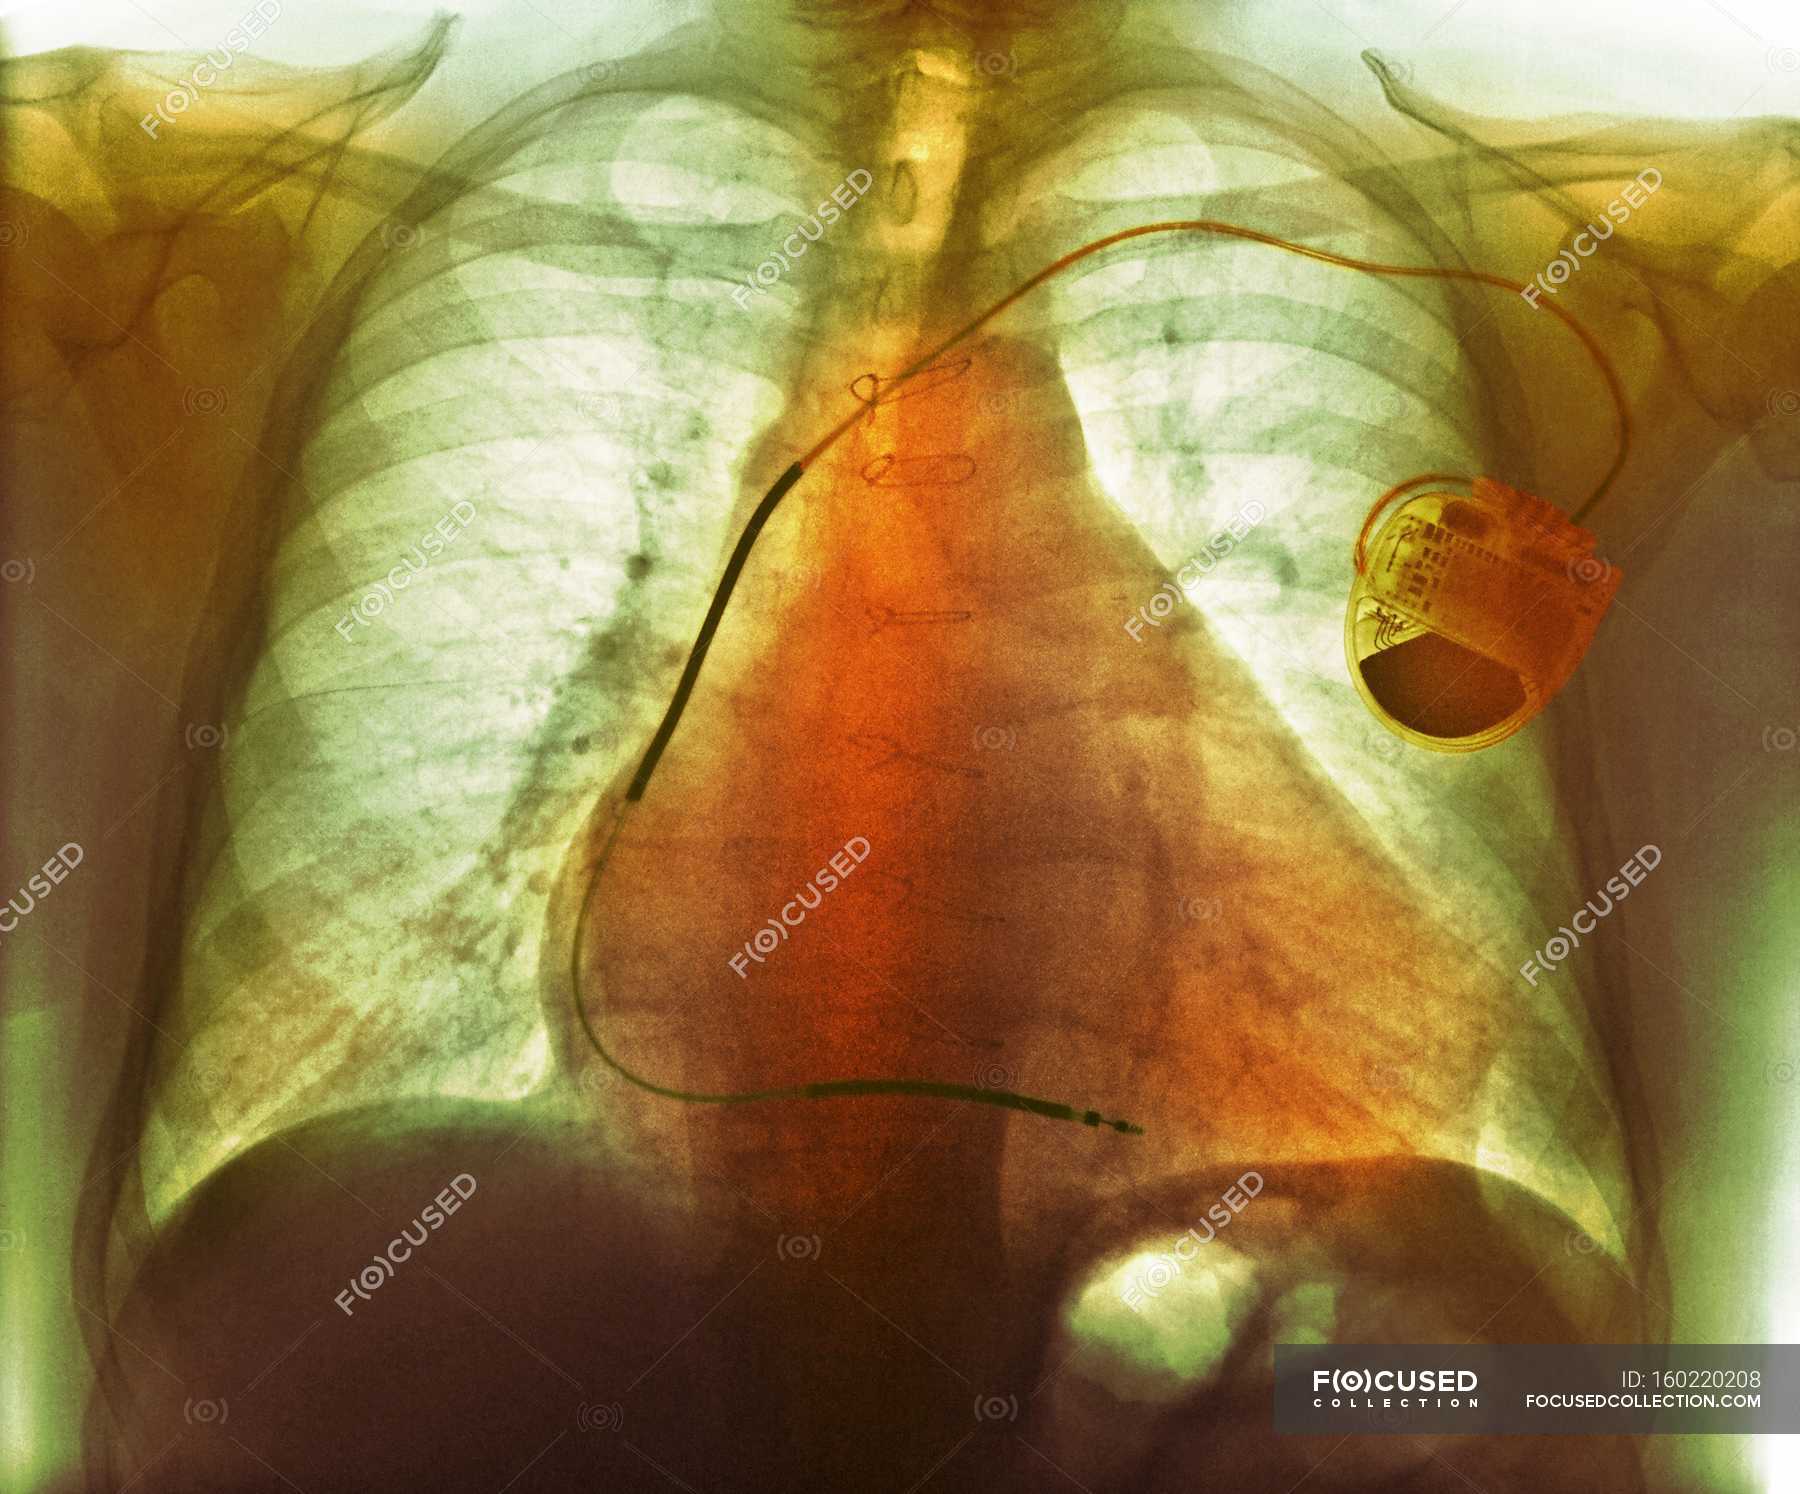

From pixels.com

Pacemaker For Heart Failure Photograph by Zephyr/science Photo Library Will A Pacemaker Help With Heart Failure An icd does not improve heart function or relieve symptoms of advanced heart failure. In this procedure, a special pacemaker makes the ventricles contract at the same time. A pacemaker monitors your heart rate and sends small and painless electrical impulses to the right ventricle of your heart to start each heartbeat. However, an icd works as a key. This. Will A Pacemaker Help With Heart Failure.